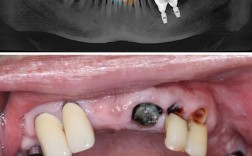

(图片来源网络,侵删)